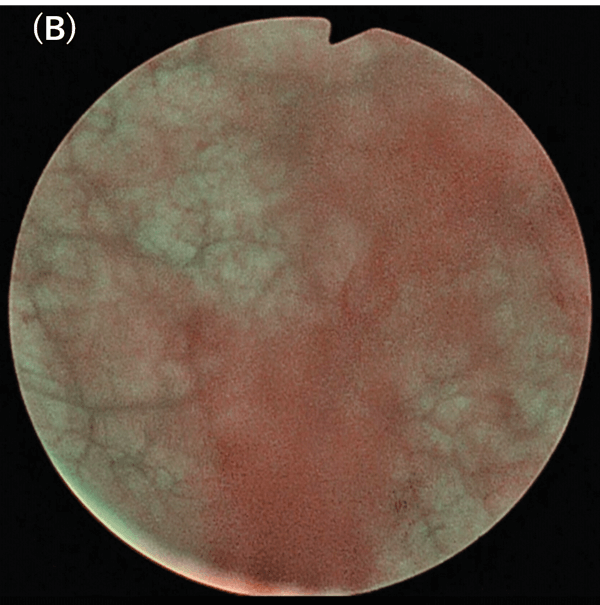

Fig. 6. NBI observations. (B) Inside the bladder. Bleeding makes the field of view dark and unclear.